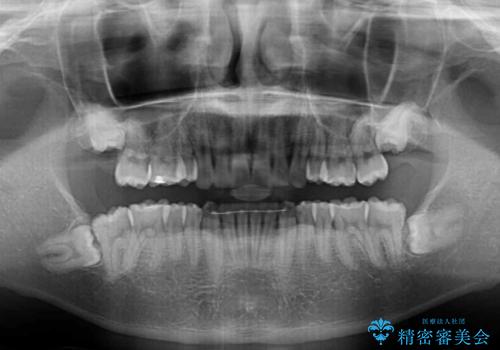

治療途中で遠方に転勤となったため、通院が困難となり治療期間が長期化してしまいました。

上顎のみの抜歯矯正をインビザラインで行う場合、奥歯の前方移動がインビザラインでは苦手のため、奥歯の咬み合わせが不十分となることがあります。

今回の治療では終了時に奥歯は接触しているものの、接触の程度は物足りないものがある状態でした。今後保定期間に少しずつ奥歯の咬合を改善させていくことになります。